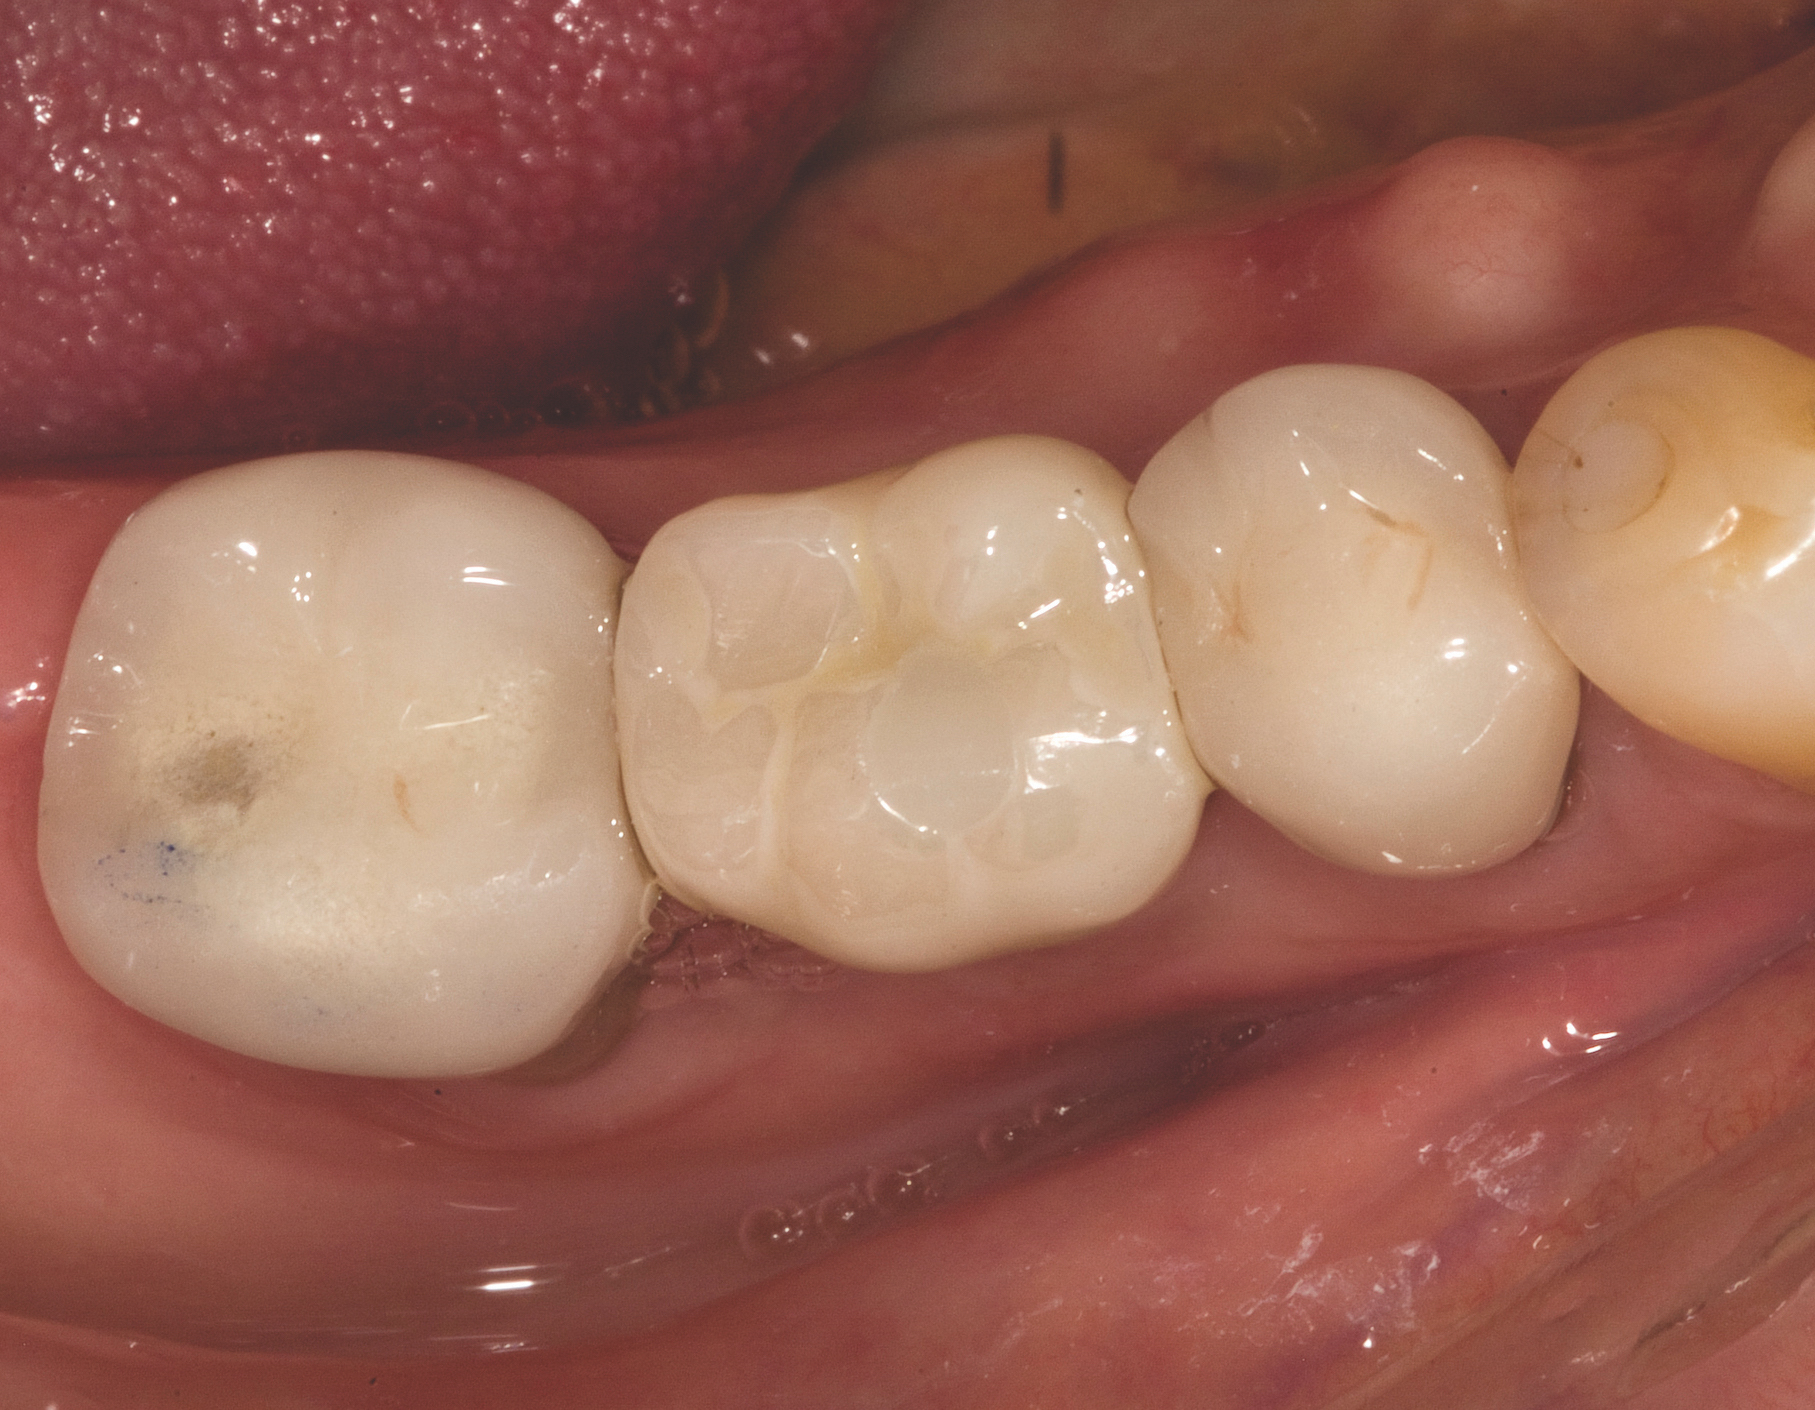

A mandibular right first molar was extracted due to an advanced Class III furcation and an irreversible pulpitis—a combination lesion. An immediate implant placement protocol was elected, and a PEEK abutment was placed on the implant (Figure 1). After 3 months of healing, a scan body was placed on the osseointegrated implant (Figure 2 and Figure 3), and an intraoral scan was taken (TRIOS Pod) (Figure 4) for the fabrication of a screw-retained crown.

Once the STL file generated from the intraoral scanner was sent to the laboratory (Figure 5), the technician used proprietary software to design the crown (Figure 6 through Figure 8), mill the crown, and digitally print a SLA model (Dental SG, Formlabs, www.formlabs.com) (Figure 9 through Figure 11), and then finish the crown on the digitally printed model. The angulated screw-channel full-zirconia crown (Nobel Biocare) (Figure 12) was seated, and contacts were evaluated intraorally and adjusted extraorally. The screw-retained crown was torqued to 35 Ncm2, and the screw access was sealed (Figure 13 through Figure 15).

Fig 3. Confirmation of seating of scan body.

Figure 3

Fig 13. Screw-retained implant crown replacing missing first molar, occlusal view.

Figure 13